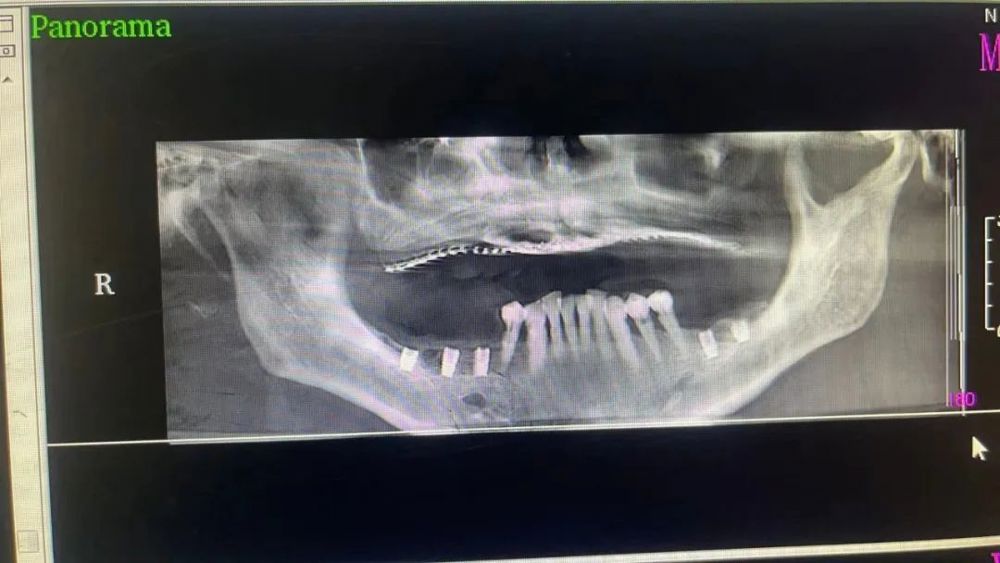

案例(lì)二

種植前 種植後